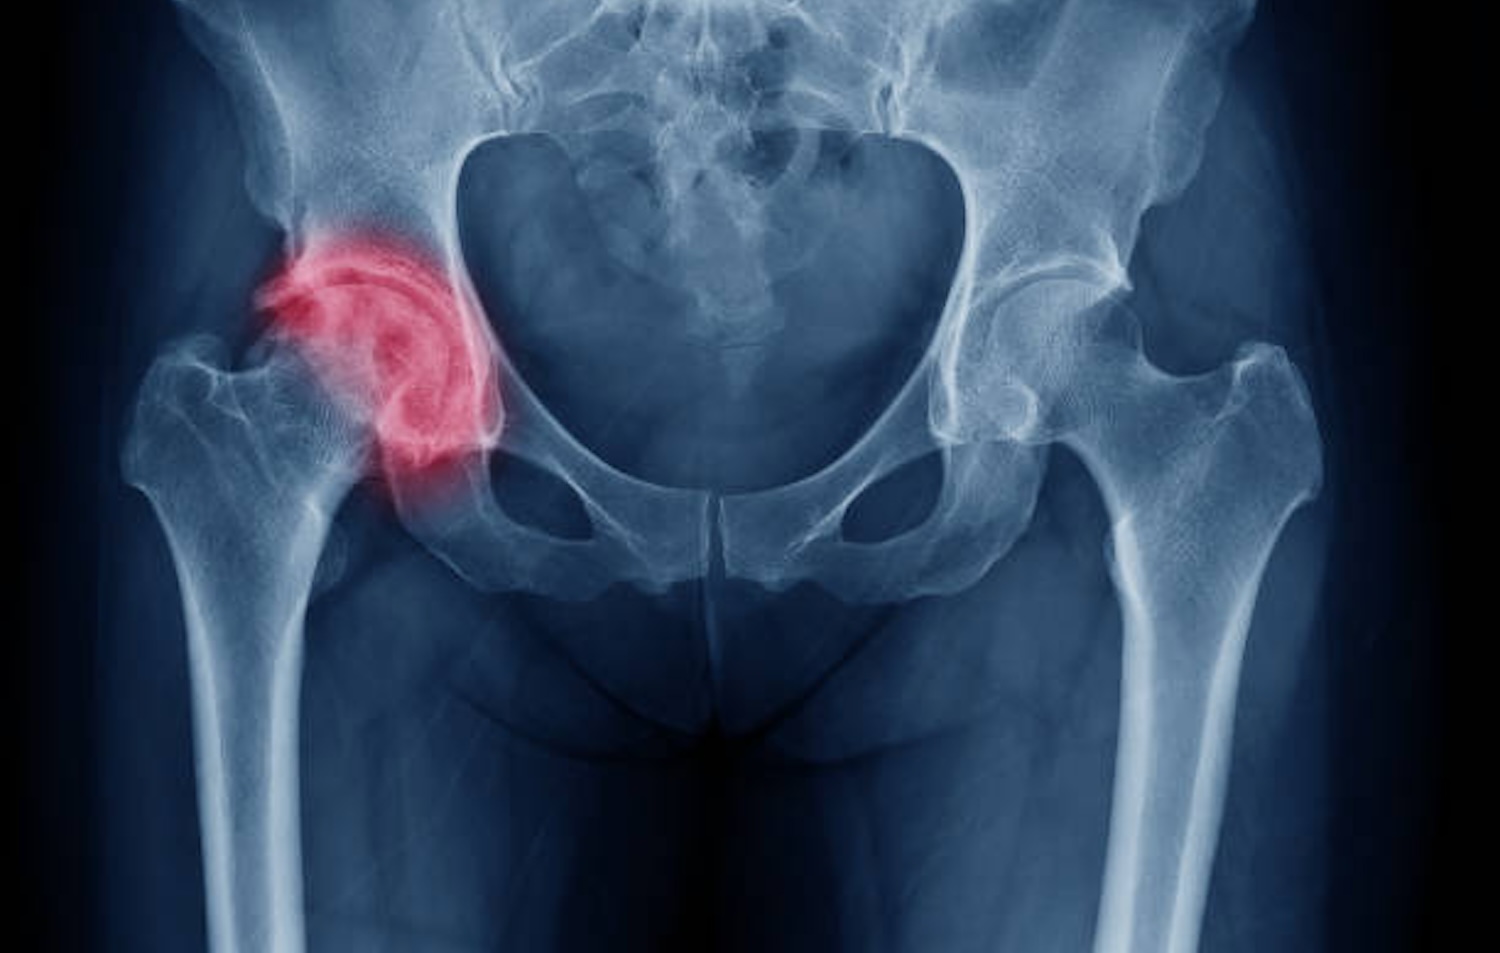

Een versleten heup komt veel voor, vooral bij ouderen. Het probleem ontstaat door artrose, een aandoening waarbij het kraakbeen rondom het heupgewricht geleidelijk afbreekt. Het kraakbeen wordt dunner, zachter en brokkelig, waardoor het gewricht minder soepel beweegt. Door het ontbreken van beschermend kraakbeen kunnen zenuwen worden blootgelegd, wat pijn en stijfheid veroorzaakt. De aandoening beïnvloedt dagelijks bewegen en vermindert de levenskwaliteit aanzienlijk.

De eerste klachten beginnen vaak met stijfheid en pijn tijdens dagelijkse handelingen. Vooral bij het opstaan uit bed of bij het traplopen is de pijn merkbaar. Het kraakgeluid dat soms uit het heupgewricht komt, is een duidelijk teken van slijtage.

Ook kan bukken en hurken, bijvoorbeeld om de veters te strikken, pijnlijk zijn. De pijn straalt vaak uit naar de lies, bil of knie, waardoor de precieze herkomst moeilijk te herkennen is.